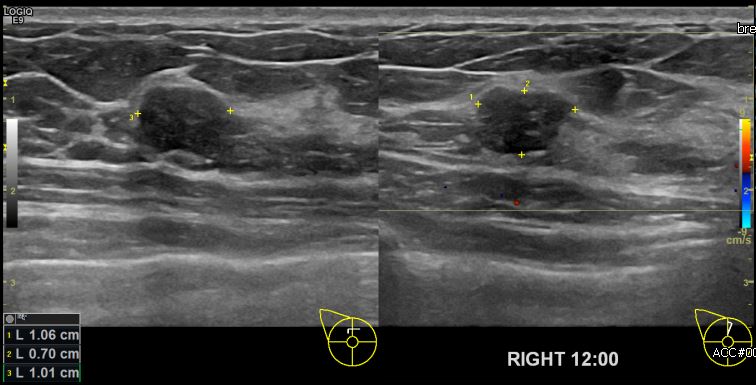

상기환자 건강검진상 이상소견으로 내원하신 50대 여성분으로 본원 초음파상

우측 유방 12시 방향에 의심스러운 멍울 조직검사 시행하여 우측 침윤성 유관암

진단 되었습니다.